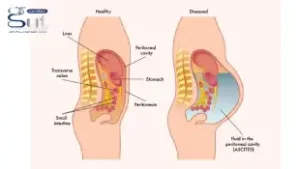

يعد مرضى التليف الكبدي الأكثر عرضة للإصابة بدوالي المريء بسبب ارتفاع ضغط الدم في الوريد البابي، مما يؤدي إلى تجمع الدم في الأوردة الصغيرة في المريء وتوسعها بشكل غير طبيعي.

مريض التليف الكبدي المصاب بدوالي المريء يواجه خطرًا حقيقيًا ومعقدًا نتيجة تطور المرض وتأثيره المباشر على الدورة الدموية داخل الكبد. إذ يُعد ارتفاع ضغط الدم البابي أحد المضاعفات الشائعة لتليف الكبد، وهو ما يؤدي إلى تكون دوالي في المريء نتيجة احتقان الدم في الأوردة المحيطة.

وفي الأشخاص الذين تم تشخيص إصابتهم بتليف الكبد، يعاني 30% منهم بالفعل من ارتفاع ضغط الدم البابي ودوالي المريء في وقت التشخيص، وما يصل إلى 90٪ ستطور لديهم خلال السنوات العشر التالية. ومع تفاقم التليف، يزداد الضغط داخل هذه الأوردة، مما يجعل الدوالي أكثر بروزًا وأكثر عرضة للتمزق والنزيف – وهي حالة طبية طارئة تتطلب تدخلاً فوريًا.

قد تترافق دوالي المريء مع دوالي المعدة، والتي قد تسبب أعراضًا مثل:

- ألم في الجزء العلوي من البطن

- قيء دموي في بعض الحالات

- براز أسود اللون melena نتيجة نزول الدم في البراز

- ضعف عام وشحوب نتيجة فقر الدم

- انخفاض ضغط الدم في الحالات الشديدة

- الشعور بالدوخة وعدم الاتزان